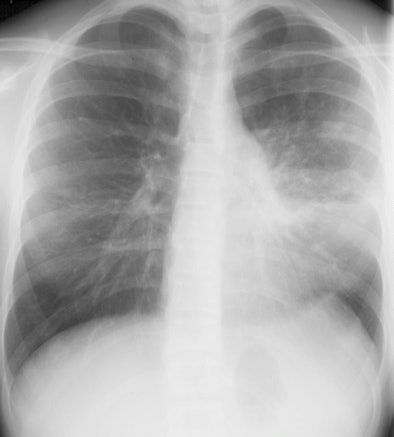

![]() |

| A 13-year-old girl with pneumonia caused by Mycoplasma pneumoniae. Chest x-ray (above) and a contrast-enhanced 1.5-tesla coronal image (below). The MR image shows patchy parenchymal changes in both lungs. Images courtesy of the Department of Radiology, Turku University Hospital. |